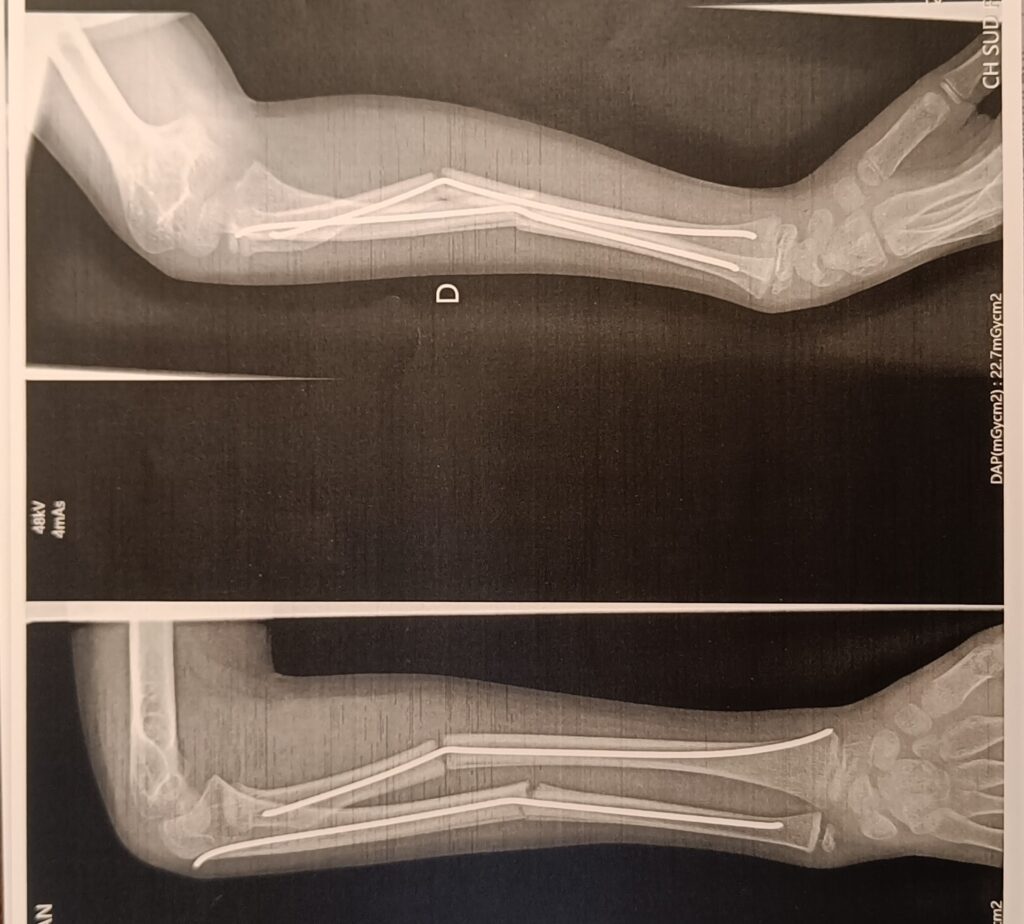

En règle générale, une fracture est décelée par radiographie, si l’œdème est trop important ou situé sur un os peu visible, un scanner ou une I.R.M sera nécessaire.

On pose une attelle si la fracture est stable et réduite. Lors d’une fracture déplacée ou complexe, une chirurgie est effectuée dans la plupart des cas.